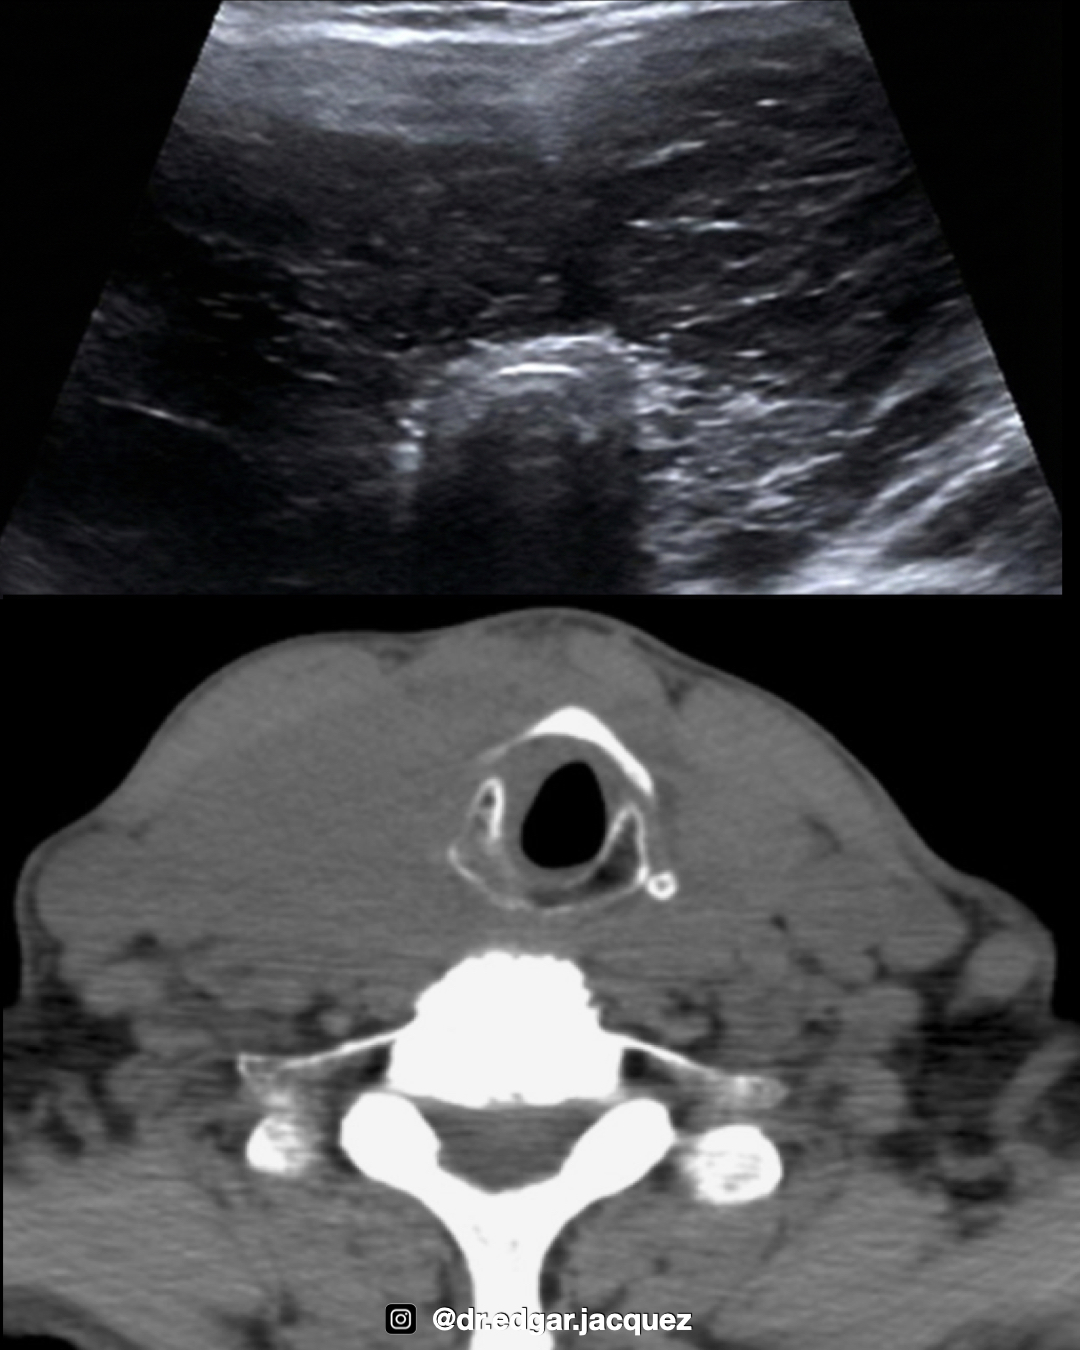

Contexto Postquirúrgico o Tiroides Atrófica

+En glándulas post-quirúrgicas o atróficas, la anatomía se encuentra distorsionada. El sistema TI-RADS solo debe aplicarse si se identifica tejido residual inequívoco que contenga un nódulo bien definido. En estos escenarios, el enfoque debe orientarse hacia la diferenciación de tejido “Viable” versus “No viable” y recurrencia locorregional.

Tejido Post-tiroidectomía

Es vital diferenciar entre tejido cicatrizal o de granulación (típicamente estable y avascular) y la recurrencia tumoral.

Semiología: La recurrencia se manifiesta como nódulos con crecimiento progresivo, márgenes lobulados y vascularidad interna detectable por Doppler.